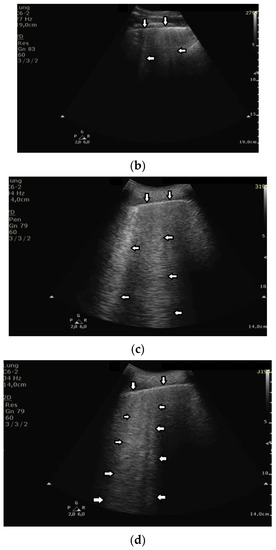

Based on clinical observations, we know that in pulmonary fibrosis, B lines often reduce their length when higher frequencies are used on a convex probe (from 2 MHz up to 6 MHz) (see Figure 4a,b). In the case of cardiac edema, the length of a B line is often stable, irrespective of the frequency modification (see Figure 4c,d) [3]. Why does the length of B lines sometimes change when varying the pulse central frequency, whereas sometimes the length does not significantly change?

Look at the entire image, and you will find the answer. When using the 2 MHz frequency, the image (Figure 4a) is brighter everywhere: the thoracic wall is brighter; the pleura line is brighter; the two lateral sides of the image (where there are no artifacts) are brighter, and the artifacts themselves are brighter. In my opinion, the problem is primarily given by the attenuation, which increases when increasing the frequency. In order to compensate such an effect, you should change the TGC. As a rule of thumb, you can consider an attenuation coefficient of 1 db/cm/Mhz. When varying the frequency from 2 MHz to 6 MHz, you are introducing an additional attenuation of 4db per centimeter. From a practical point of view, when using the 6 MHz frequency, the probe receives a signal from the depth of half a centimeter, whose amplitude is less than half the amplitude of the signal it would receive from the same depth if a 2 MHz pulse were used. Moreover, it is worth noting that the ratio between the amplitudes of the two temporal signals s6(t) and s2(t) (the echoes received by the probe) decreases exponentially when the delay t increases.

The answer is a bit more complex when cardiac edema is considered. In the case of fibrosis, larger acoustic traps and wider linking channels are, in general, expected that reradiate almost the entire power spectrum of the trapped acoustic pulse. In this case, attenuation is probably the main factor that influences the artifact length when varying the frequency. Therefore, the artifact length decreases when increasing the pulse central frequency since attenuation increases when increasing the frequency. On the contrary, in the case of cardiac edema, smaller acoustic traps and narrower linking channels are expected at the early stages of the pathology. Smaller traps can reradiate only a few harmonics, and the overlapping between the pulse spectrum and the spectral signature of the trap affects the artifact length much more than the attenuation factor. In these cases, the trap response to pulses with different frequencies is unpredictable.

Figure 4. (a) Pulmonary fibrosis in the course of interstitial lung disease: down arrows—pleural line; left arrows—B line artifact observed at 2 MHz frequency. (b) Pulmonary fibrosis in the course of interstitial lung disease: down arrows—pleural line; left arrows—vertical artifacts observed at 6 MHz frequency. The image was obtained from the same patient and identical assessment site as in Figure 4a. (c) Cardiac edema: down arrows—pleural line; left arrows—B-line artifacts observed at 2 MHz frequency. (d) Cardiac edema: down arrows—pleural line; left arrows—B-line artifacts observed at 6 MHz frequency. The image was obtained from the same patient and identical assessment site as in Figure 4c.